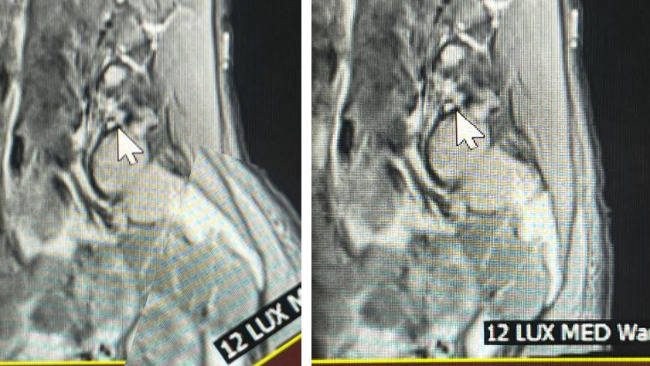

Kasia upadła na plecy, wstała i samodzielnie dotarła do domu. Następnego dnia zaczęły się objawy neurologiczne i bólowe. W szpitalu nie rozpoznano złamania i dopiero po wielu błędnych diagnozach stwierdzono poprzeczne złamanie kości krzyżowej z przemieszczeniem i uszkodzeniem korzeni nerwowych.

Na operację było za późno, bo kość się zrosła w nieprawidłowej pozycji. Od tamtego zdarzenia Kasia żyje w bólu, nie może siedzieć, przez większość dnia chodzi o lasce lub kuli, kręgosłup się wykrzywia, balans ciała jest zaburzony, dno miednicy nie funkcjonuje prawidłowo. Ciało Kasi się zapada, a ona ugina się psychicznie pod ciężarem bólu i ograniczeń.

Kasię czeka osteotomia kości krzyżowej bardzo trudna, rzadka i wymagająca technicznie operacja, która ma przywrócić prawidłową anatomię i stabilność miednicy i sprawność kręgosłupa. To jedyna szansa dla Kasi na zatrzymanie postępu choroby i powrotu do normalnego życia. To nie tylko szansa dla Kasi, ale dużej grupy pacjentów ze złamaniami kości krzyżowej.